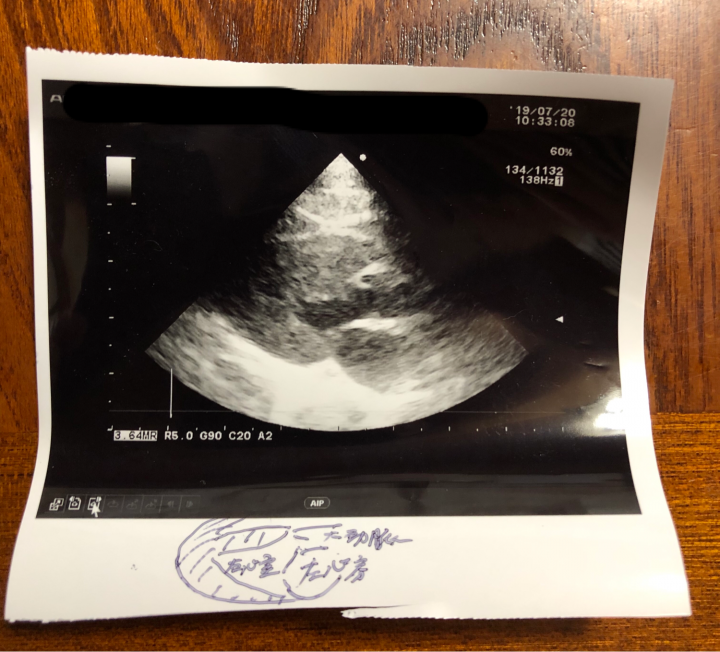

心筋の厚さも4ミリ(6ミリから肥大型心筋症)で正常。

大動脈と左心房が1:1.6

が正常でそれも大丈夫、

あと、初めてなんですが…

記念に

って獣医さんからエコーの写真もらいました。

記念にって…

どういう記念なんだろう🤔